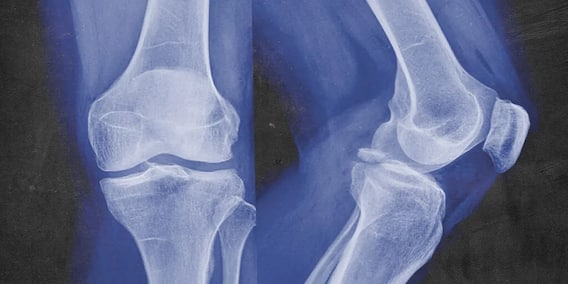

নয়া দিল্লি: হাড়ের সমস্যা (Bone Problem) নিয়ে ভোগেন অনেকেই। বিশেষত বয়স হলে। হাড় ক্ষয়ে যাওয়ার সমস্যায়ও নতুন নয়। বয়স বাড়লে এই সমস্যা যেমন প্রকট হয়, তেমন সমাধান সূত্রও প্রায় নেই। সেই সুরাহা দিতেই এবার আইআইটি কানপুরের (IIT Kanpur) চিকিৎসক আবিষ্কার করে ফেললেন একটি ইনজেকশন। যা দিয়ে ক্ষয়ে যাওয়া হাড় আবার নতুন করে তৈরি (Bone Regeneration) হবে শরীরে।

জানা গিয়েছে, একটি রাসায়ানিক মিশ্রণ তৈরি করেছেন তিনি। সেটি ক্ষয়ে যাওয়া হাড়ের নির্দিষ্ট স্থানে ইনজেক্ট করলে সেখানে ফের নতুন করে হাড় গজাবে। এমনই নয়া প্রযুক্তি। এই দুই মিশ্রণ আসলে বায়োঅ্যাকটিভ অণুর বাহক হিসেবে কাজ করবে। যিনি এই প্রযুক্তি তৈরি করেছেন সেই বায়োসায়েন্স এবং বায়োইঞ্জিনিয়ারিং বিভাগের অধ্যাপক অশোক কুমার বলেন, "আসল হাড় তৈরি হবে না তবে আসলের মতোই কৃত্রিম হাড় তৈরি হবে ক্ষত স্থানে।"

আইআইটি অধ্যাপক বলেন, "সাধারণত, হাড়ের টিবি বা ক্যান্সারের ক্ষেত্রে, রোগীদের আক্রান্ত অঙ্গ কেটে ফেলা ছাড়া আর কোন উপায় থাকে না। কারণ হাড়ের পুনঃবৃদ্ধির কোন আশা থাকে না। একই সময়ে, দুর্ঘটনায় হাড় ভেঙে যাওয়ার ঘটনায় একই অবস্থা হয় চিকিৎসকদের। অনেকসময় উরু বা শরীরের অন্য কোনও অংশ থেকে হাড়ের টুকরো অপসারণ করে প্রতিস্থাপন করা হয়। কিন্তু সেক্ষেত্রে অন্য রোগেরও সম্ভাবনা থাকে।"

অধ্যাপক বলেন, "এটি জয়েন্টের সমস্যা থেকে মুক্তি পেতে সাহায্য করতে পারে। হাড় গঠনের পর, ন্যানো-হাইড্রোক্সিপেটাইট এবং ক্যালসিয়াম হেমিহাইড্রেট শরীর থেকে স্বয়ংক্রিয়ভাবে নির্গত হবে।"